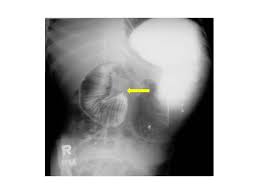

Symptoms of persistent vomiting with abdominal distention epigastric tenderness and tympanic percussion note usually beginning 6 to 8 days after surgery or the application of a body casting but may occur up to 40 days thereafter. Superior mesenteric artery syndrome is a potentially life-threatening condition that affects the gastrointestinal tract. Congenital abnormalities weight-related conditions andor surgical procedures that result in alterations of the anatomy of the spine and surrounding structures including.

Acute Gastric Dilation Caused By Superior Mesenteric Artery Syndrome Postgraduate Medical Journal